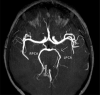

Arterial ischemic stroke is a rare but significant cause of neurological deficits in childhood. Even though there is a variety of risk factors, identifying the etiology can sometimes be a hard diagnostic challenge. Arteriopathies in general, and more specifically, arterial dissection is one of the uncommon pathologies that can cause incidents of pediatric stroke. We report a rare case of a young adolescent with posterior cerebral artery dissection after excessive consumption of caffeine, contained in energy drinks, only hours before the onset of neurological symptoms. A complete neuroimaging evaluation (MRI, intracranial US and digital subtraction angiography) at the admission and during the follow-ups supported the diagnosis of arterial dissection possibly caused by caffeine overconsumption.